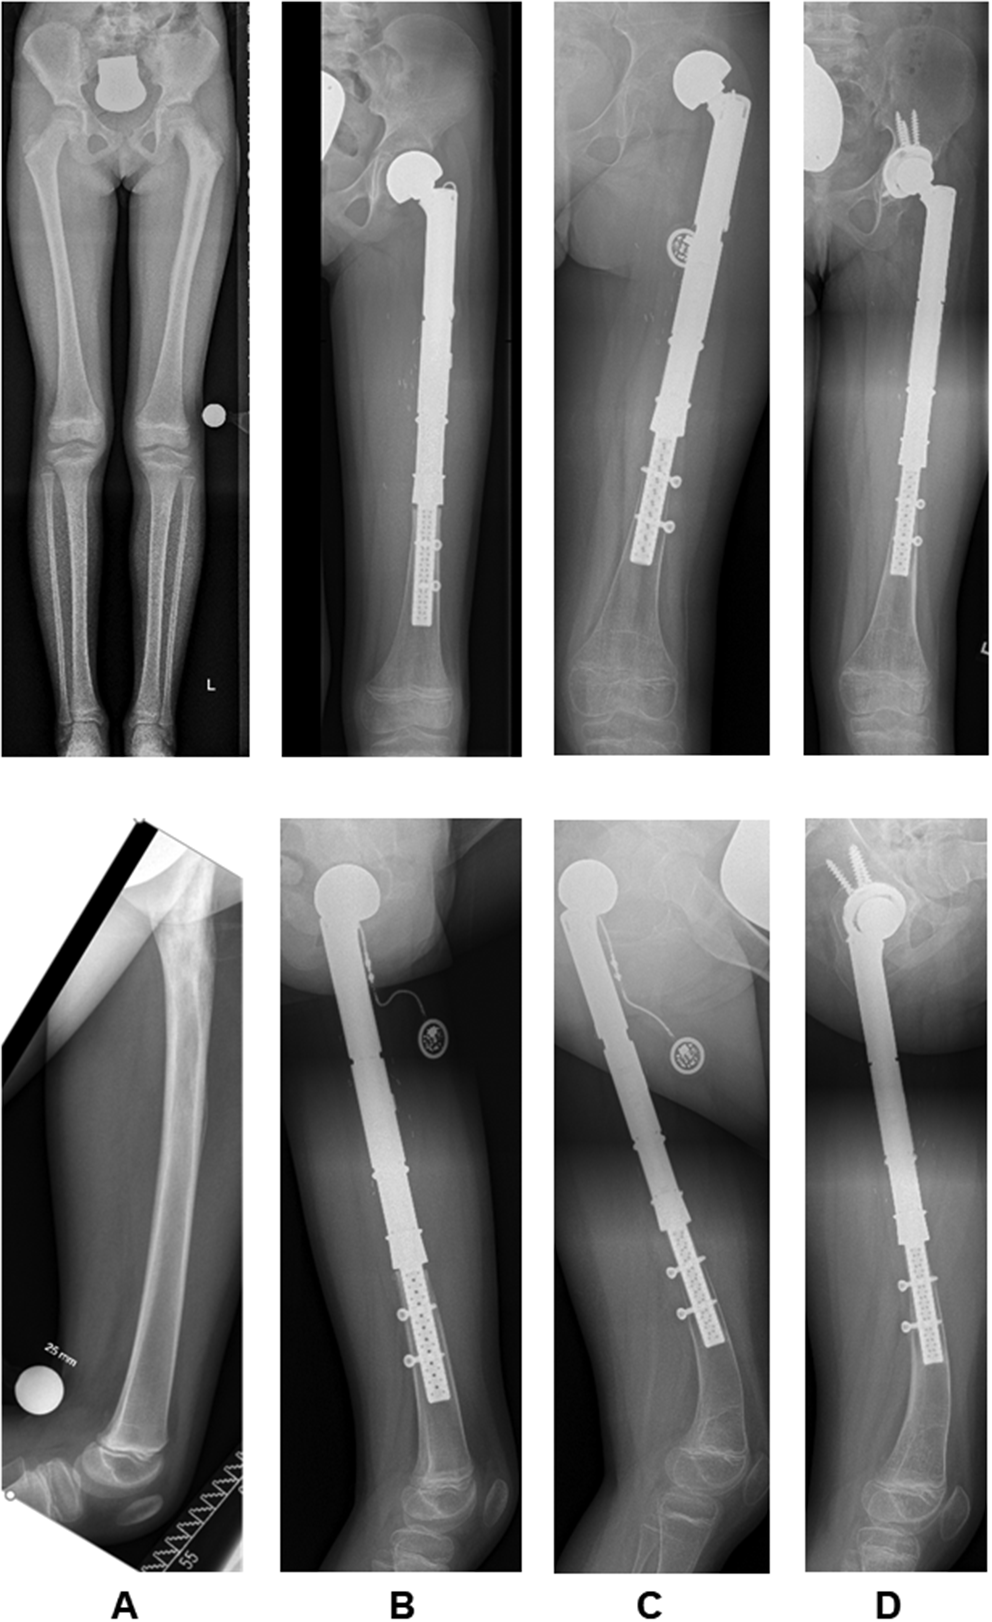

Secondary hip dysplasia after proximal femur replacement was observed in seven patients (n = 7/14; 50%; intraarticular n = 7/12; 58.3%) who were aged < 10 years (range 4–8 years) at the time of primary reconstruction (Fig. 2a/b and 3). As a result, four of these patients (n = 4/7; 57.1%) developed secondary hip dislocations that needed to undergo revision operations after a mean of 26 months (range 16–30 months) after the primary operation (see also Table 1). Soft tissue reconstruction in these cases was performed with or without an attachment tube in three and four cases, respectively. While two patients were reconstructed by endoprosthetic replacement of the dysplastic acetabular socket (#1 and 8), two other patients underwent triple pelvic osteotomies to address hip dysplasia and dislocation at first (#3 and 6). Persistent or rebound hip dysplasia occurred in both cases. Attempted open or closed reductions and acetabular deepening using a reamer did not succeed in both patients and ultimately led to endoprosthetic acetabular socket replacements 24 and 49 months after triple pelvic osteotomy (Fig. 3). Of the other three patients who developed secondary hip dysplasia, two patients did not progress to hip dislocation (#7 and 9). However, patient #9 died of disease 48 months after the primary reconstruction. Patient #10 developed secondary hip dislocation but has not undergone revision surgery so far (see also Table 2). This patient is suffering from delayed physical growth and complex bilateral limb deformities following a delayed fine and gross motor development after the completion of chemotherapy.

Fig. 2

8-year-old patient (#1) with a Ewing’s sarcoma of the left proximal femur. A.p. and lateral x-rays prior to (A), 3 (B), 26 (C) and 33 (D) months after the 1st and 11 months (D) after the 2nd operation. Presentation of secondary hip dysplasia, lateralization and dislocation of the bipolar head in C. Presentation of stress shielding in C and D. Development of a 13° procurvatum flexion deformity in the lateral plane (C) and spontaneous correction following the 2nd operation (D)